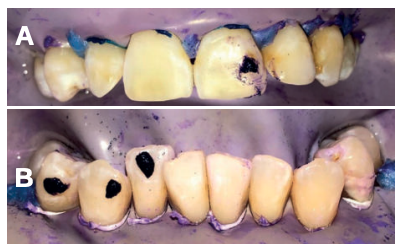

La fluorosis dental es una condición irreversible originada durante el desarrollo dental que genera pigmentaciones intrínsecas, alteraciones en el esmalte manifestadas a manera de manchas blancas, amarillas o marrones, que perjudican la estética y repercuten en el desenvolvimiento social. El presente reporte de caso clínico describe la combinación de los procedimientos de microabrasión y blanqueamiento dental, como alternativas en la eliminación de pigmentaciones dentales. Después del diagnóstico de la patología, verificación de ausencia de lesiones pulpares y caries, una explicación minuciosa a la paciente y obtención del consentimiento informado, se realizó limpieza de las superficies dentales y, bajo aislamiento absoluto, se procedió a realizar la técnica de microabrasión mediante ácido clorhídrico al 6,6% siguiendo las instrucciones del fabricante. Concluido el procedimiento y, observando que era posible mejorar aún más la estética, se decidió ejecutar el procedimiento de blanqueamiento dental, a base de peróxido de hidrógeno al 40% en el consultorio, seguido por peróxido de carbamida al 10% aplicado en el domicilio. Al finalizar el tratamiento se observó uniformidad en el color dental, conjugados con una evidente mejora en la calidad de vida y relación social de la paciente.

La combinación de procedimientos, como el reportado en este caso, constituye una excelente alternativa de tratamiento para eliminar pigmentaciones fluoróticas moderadas.